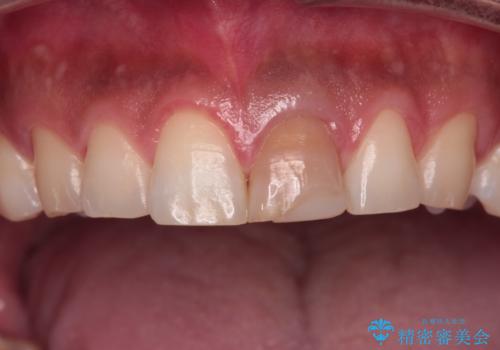

- 神経を取り除いたことで変色した前歯を気にして来院された患者様です。

根管治療はやり直さずに、ファイバーポストを使用した土台を植立してオールセラミッククラウンにて補綴することとしました。

神経を取り除いた歯は時間とともに変色してきます。

クリーニングやホワイトニングでは改善できないため、オールセラミッククラウンなどによる補綴治療が必要となります。